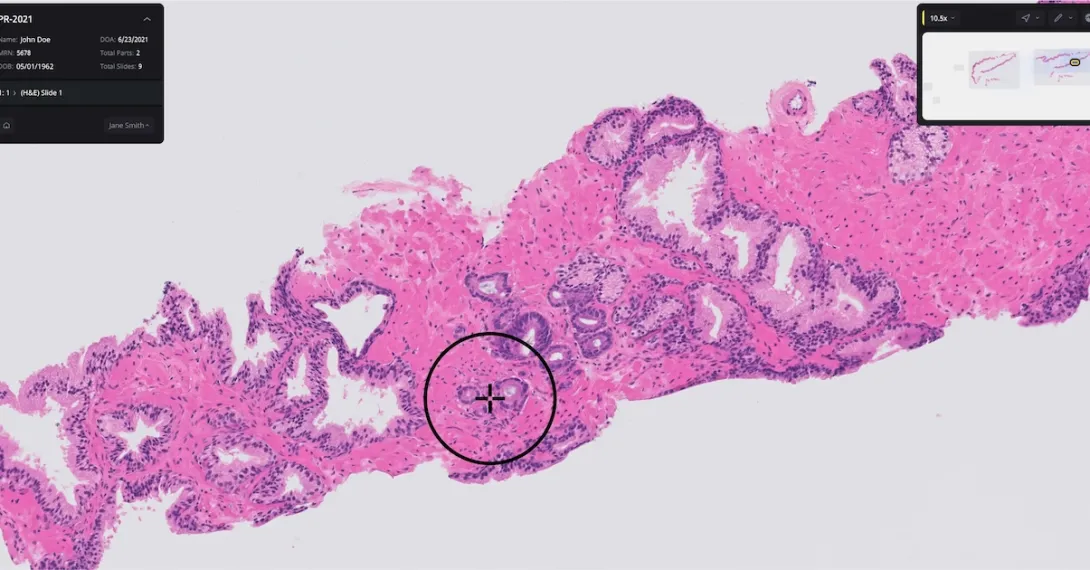

The Paige Prostate software analyzes digitized biopsy slides and identifies areas that could be cancerous for the pathologist to review further.

Authorization for Paige Prostate was based on a clinical study where 16 pathologists examined 527 prostate biopsy slides. The software improved the pathologists’ ability to detect cancer on individual slide images by an average of 7.3% (from 89.5% to 96.8%).

Further, pathologists using Paige’s software had a 70% reduction in false-negative diagnoses and a 24% reduction in false-positive diagnoses. Paige Prostate also helped boost nonspecialist pathologists’ diagnostic accuracy to the same level as prostate specialists who were not using the software.